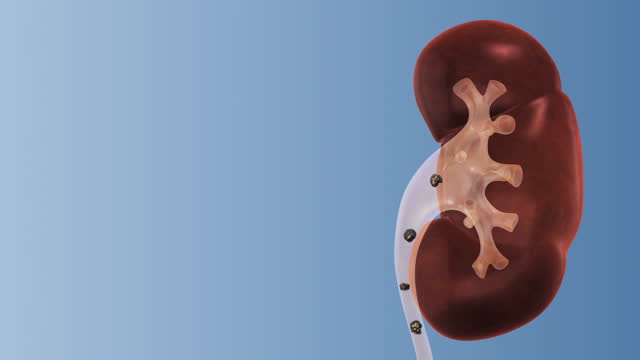

1. 소변에서 거품이 생기는 현상

소변에서 거품이 많이 생길 때, 이는 단백뇨(단백질이 소변으로 빠져나가는 현상)가 있는지 의심해야 합니다. 신장의 기능에 문제가 생겼을 때 발생할 수 있으므로 소변검사를 통해 확인이 필요합니다.

2. 소변에서 피가 나올 때

혈뇨, 즉 소변에서 혈류가 나오면 이는 신장의 염증 또는 다른 문제의 가능성이 있습니다. 소변이 붉게 나온다면 반드시 의사의 진단을 받아야 합니다.